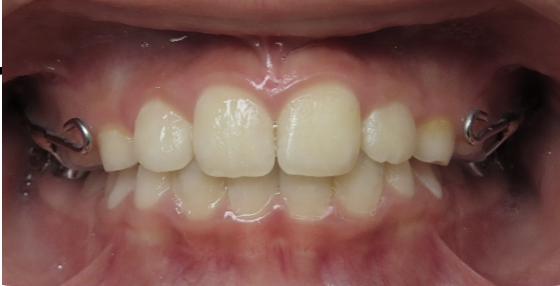

underbite corrected by expansion

Before

After